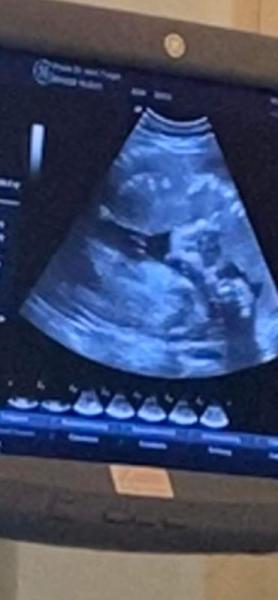

Hallo, wir sind in 34. SSW aber est ist noch immer nicht ganz klar oder wir ein Junge oder Mädchen bekommen werden.. Heute sah im Ultraschall so aus..was meint ihr? Bis jetzt eurde immer Junge gesagt

Was sagt der Arzt? Ich habe nur Jungs und da sieht mann eindeutig den Kleinen Mann. Auf deinem Bild würde ich nix in der Richtung sagen, aber vielleicht hält er ihn auch in der Hand. Und denkt sich nur verrate Ich es die letzten Wochen auch nicht mehr. Aber die Hauptsache ist ja das alles andere stimmt und gut ist.

Hallo, für mich eindeutig ein Mädchen. So sah es bei meiner Tochter aus und bei meinen drei Jungs, wovon einer in den nächsten Tagen geboren wird, sah man eindeutig das es Jungs werden.

Ich habe ein Junge und ein Mädchen für mich sieht das sehr nach Mädchen aus